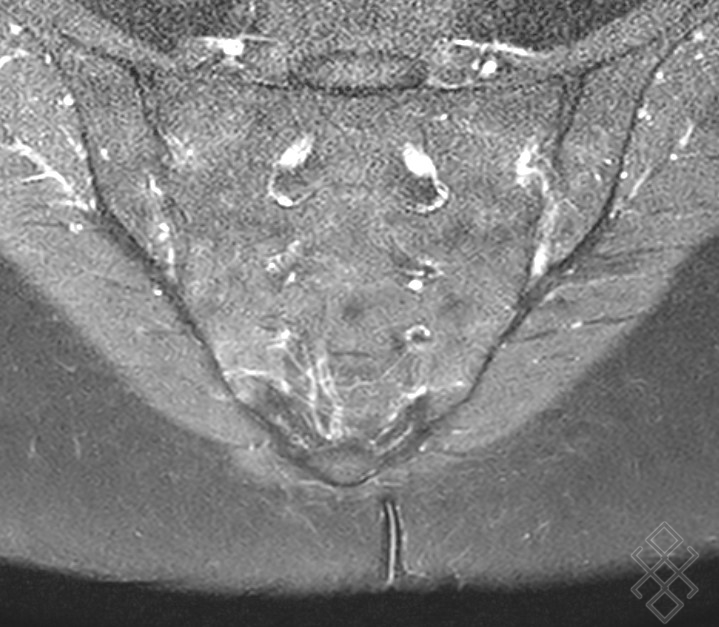

Sacro Iliite Stade 4

L'atteinte sacro-iliaque radiologique, la sacro-iliite stade 2 bilatérale ou stade 3, est indispensable pour porter le diagnostic de spondylarthrite ankylosante, selon les critères de classification de New York modifiés (tableau 19.4) L' inflammation de l'articulation sacro-iliaque, souvent appelée sacro-iliite, est une affection douloureuse qui affecte l'articulation située entre le sacrum et l'os iliaque du bassin Stade 3 : sacro-iliite modérée (sclérose nette des deux cotés, aspect flou et indistinct des bords, érosions, perte de l'espace articulaire) Stade 4 : fusion complète ou ankylose des sacro-iliaques.

Coupe axiale des sacroiliaques montrant une sacroiliite bilatérale.... Download Scientific. On peut voir, tardivement des érosions des bords de l'articulation (aspect irrégulier) qui évoluent vers la disparition de l'articulation. Certains signes permettent de faire la différence entre les deux affections